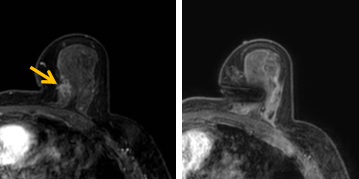

患者李女士磁共振檢查發現右乳內側高度可疑病變,病變小摸不到,超聲和X線攝影(鉬靶)都看不到,怎么辦?要想明確病變性質,必須進行磁共振引導下精準足量的活檢,但是這種技術操作難度大、軟硬件要求高。

經過仔細查體并分析所有影像資料,陳寶瑩發現,病變靠近胸大肌,容易造成術中損傷。患者乳房較小,病變在內側,導致乳房不易固定,進針難度大,與患者充分溝通后,陳寶瑩帶領團隊,制定了細致的操作方案,術中,醫護團隊反復調整體位和固定架的角度及方向,利用隔離技術保護好周圍組織。受乳房形態和病變位置的限制,醫生只能蹲著、跪著進行操作,經過30多分鐘終于順利完成,精準獲取了足量的組織,而且一針到位,創傷小、出血少,患者沒有任何不適,做完即回家休息。幾天后,病理證實是一種特殊類型的早期乳腺癌,為后續進一步治療方案的制訂提供了準確依據。

陳寶瑩教授介紹,乳腺磁共振微創診療技術是針對磁共振發現的可疑病變,進行磁共振引導的導絲定位、旋切活檢、靶釘植入及消融治療的微創診療技術。磁共振特有的多模態和功能成像,不但能顯示出更多其他檢查發現不了的可疑病變,而且能顯示出病變準確的范圍和活性區域,因此MR引導的乳腺病變真空輔助旋切技術相較于其他常規活檢技術,具有更精準、活性成分取材充足的特點,明顯降低了病理的假陰性率,提高了準確性。